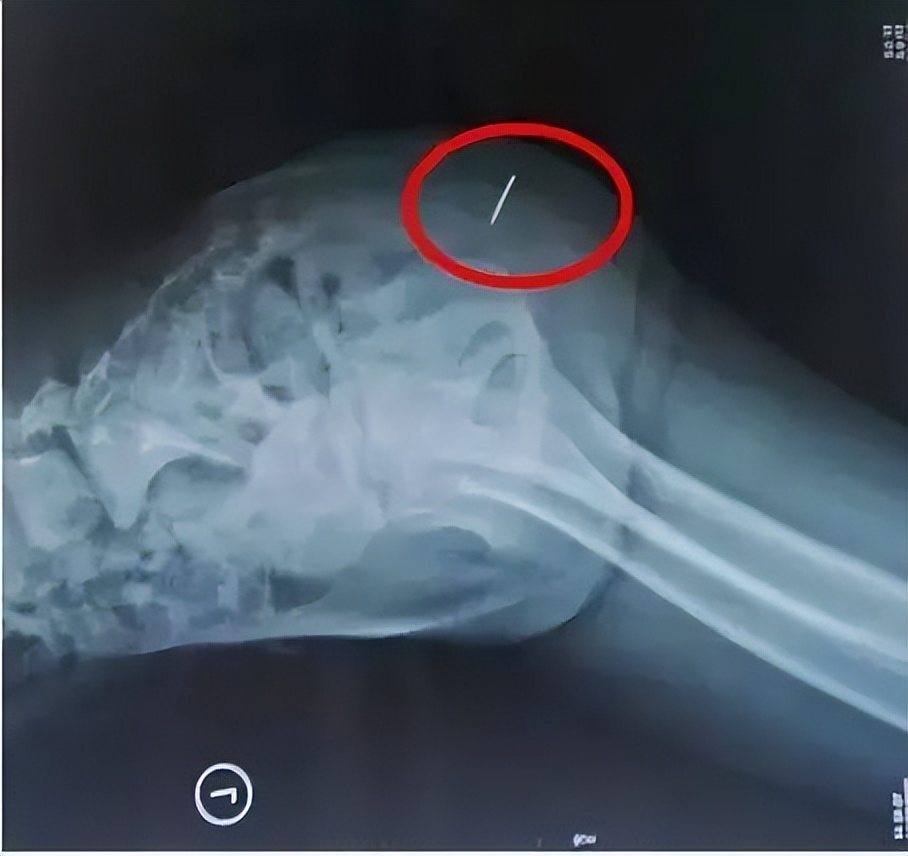

医生听完妈妈的话就让孩子躺在病床上检查一下,当医生的手碰到孩子裤子时孩子就喊疼,并且不让医生触碰。医生只好拿来小剪刀,把裤子直接剪开查看。结果发现孩子大腿这个地方有一块儿红肿,摸上去有点发硬的感觉。据医生的判断,孩子大腿里面肯定有异物,要不然孩子不会这么疼,说完立马就让孩子去拍CT检查。

当医生拿到结果后才发现,孩子大腿里面有一根针,直接插到了大腿中间,只差两厘米就要靠近骨头了,情况非常危险,需要立即手术取出。经过长达两个小时的手术治疗,小女孩大腿里面的钢针终于取了出来。缝合上创口后,医生就把取出来的钢针拿给了妈妈看,就是她导致孩子大腿红肿不能走路一碰就疼的原因。